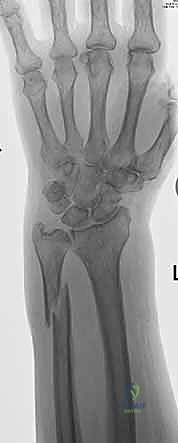

استخدام الأشعة السينية في التشخيص

1. الأشعة السينية (X-rays): بوضعيات متعددة (أمامية خلفية، وجانبية دقيقة). الوضعية الجانبية الحقيقية (True Lateral) حاسمة لاكتشاف أي خلع جزئي في المفصل (DRUJ).

2. الأشعة المقطعية ثلاثية الأبعاد (3D CT Scan): تُستخدم في الكسور المفتتة أو كسور رأس الزند المفصلية المعقدة، حيث تعطي خريطة دقيقة للجراح قبل الدخول لغرفة العمليات.

3. الرنين المغناطيسي (MRI): يُطلب عند الاشتباه القوي بوجود تمزقات في الأربطة والمركب الغضروفي (TFCC) التي لا تظهر في الأشعة السينية.

الأشعة المقطعية توفر تفاصيل دقيقة للكسر

صور الرنين المغناطيسي لتقييم الأربطة